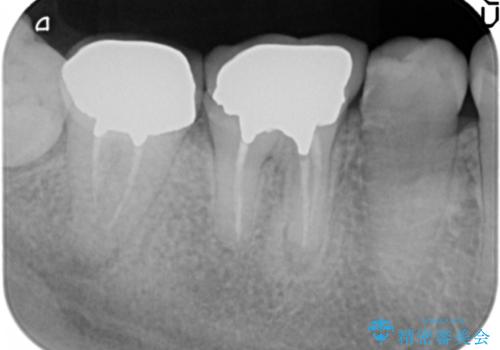

奥歯は既に根管治療が為されクラウンを装着する必要性がある状態ですが、歯の高さが低くクラウンの安定性・強度を担保するために歯周外科を行う治療計画としました。

歯周外科を行うことで、歯ぐきの位置を下げ歯の高さを作り出し安定したクラウンの装着が可能となります。また同時に舌の邪魔となっていた骨隆起の除去を行うこととしました。